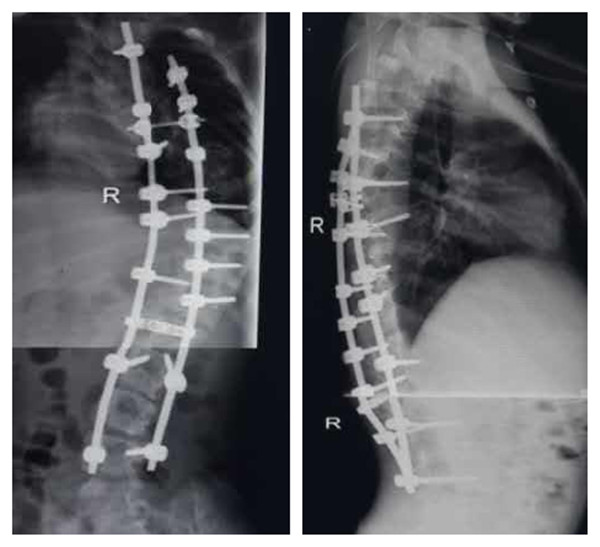

手术后X片

手术全程在诱发电位严密监测下进行,在严密保护脊髓的前提下,将脊椎一节节打断、截骨,再重新排列、固定。因脊柱畸形严重,脊柱临近都是大血管和神经,如此大范围脊柱矫形,风险极大,术中稍有不慎,无论是术中操作,还是骨片,都有可能损伤大血管造成大出血,危及生命,所以手术的每一步都要慎而又慎。常规固定方式无法完成,只能凭丰富的经验探索进行,并根据情况进行必要的术中透视。在完成椎体截骨时,脊髓也要完成近120度的变位,此时极易损伤神经,风险极大,稍有不慎都会造成患儿终身瘫痪,双下肢丧失运动及感觉功能,并出现大小便失禁等严重后果,每一步都像走钢丝一样,步步为营,甚至都不敢大幅度的呼吸,每一步都要做到轻、准、稳,随时听取神经监测报告情况,术中连续监测神经传导速度,判定神经功能,为避免手术中的神经损伤保驾护航。矫形由患儿颈后部到腰下段的脊柱全段,术中矫正脊柱畸形角度约120度。在整个手术团队的共同努力下,经过近10小时艰苦卓绝的紧张手术,取得手术的最后成功。

人心齐,泰山移,团结和谐的手术团队是手术成功的基石,该患儿术后即可平卧,背部大驼背畸形显著改善,双下肢感觉、运动良好,自解小便,现在可以骄傲的站直了,目前正在进一步的康复中。